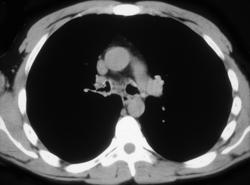

Calcified Pericardium